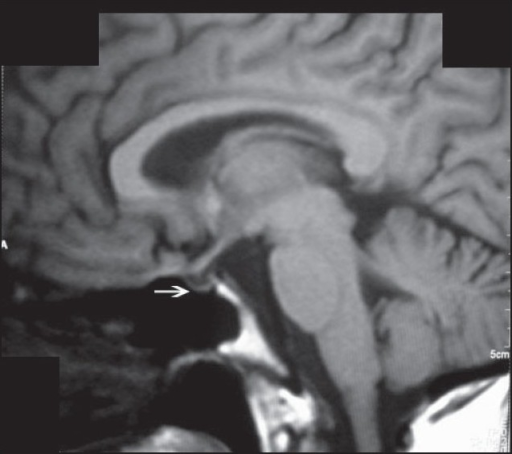

What's the Diagnosis?